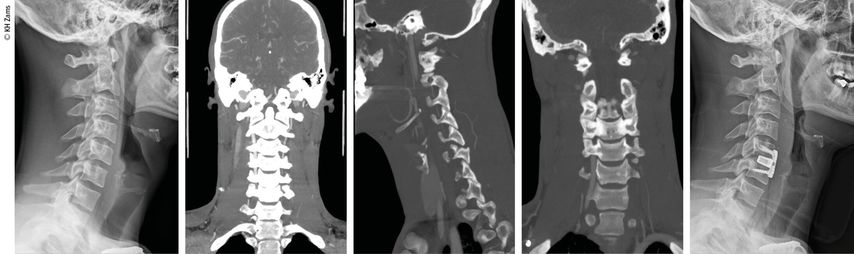

Abb. 2: Fallbeispiel: Mann, 57a, Z.n. Fahrradsturz, stabile Fraktur des Proc. artic. C2 r. mit Dissektion der A. vertebralis r. mit asymptomatischem Substanzdefekt im hinteren Stromgebiet (cMRT), Heparintherapie initial, anschließend APT

Abb. 3: Mann, 30a, Z.n. Snowboardsturz, Rotations-/Subluxationsverletzung C5/6 mit Dissektion der A. vertebralis r.; Zervikobrachialgie mit sensiblem Defizit; OP unter Heparintherapie, APT für 3 Monate

Abb. 4: Mann, 28a, Z.n. Schisturz; instabile Teardrop-Verletzung mit Dissektion A. vertebralis l.; Zervikobrachialgie mit Dysästhesie C6, mehrere kleine embolische Infarkte vertebrobasilär mit Koordinationsstörung; OP + Heparintherapie initial, anschließend APT